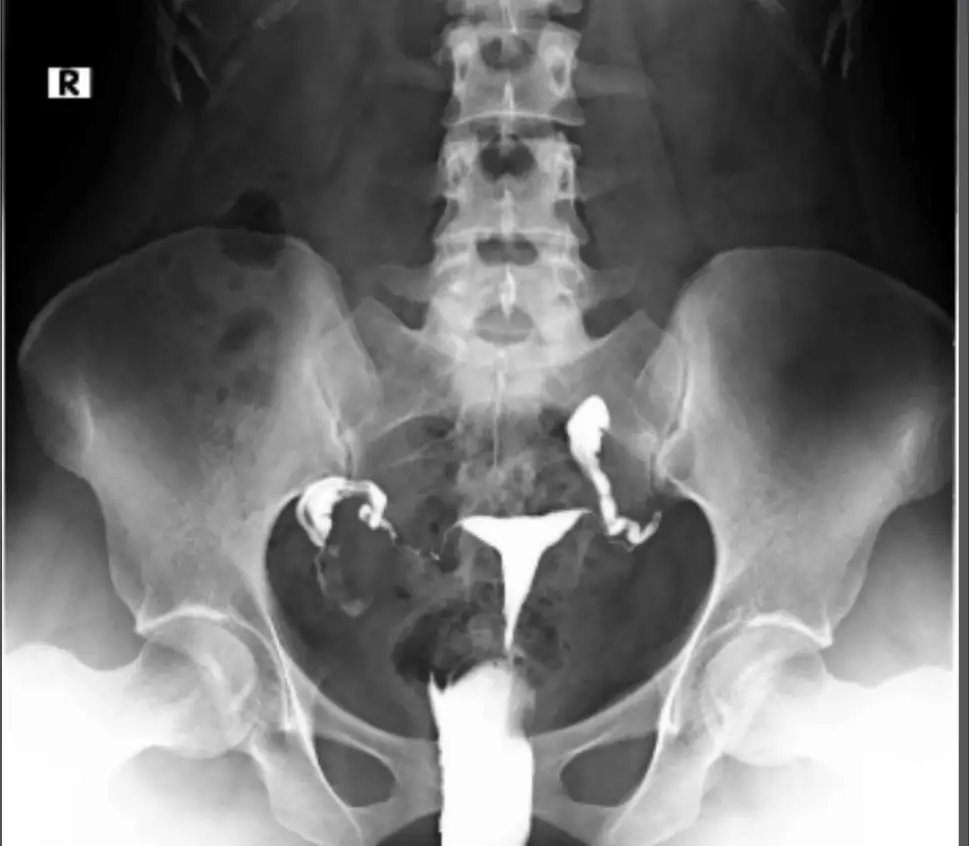

selam canım ne zamandır istiyordunuz ? eş faktöründen dolayı aşılama önermez sanırım, sen filmi yeni mi çekilmiştin görüntü var mı filmin atabilir misin bi merak ettim. hidrosalpenkste laparoskopi öneriyorlar o tüpü alıp içindeki sıvı rahime yayılıp embriyo tutunmasına zarar vermesin istiyorlar. tüpte olsa sanırım öncelikle laparoskopi ister doktorun. 3 ay sonra duruma bakacak derken tekrar mı film çekileceksin ?Kızlar eşim de morfoloji%1 ben de tek tarafta hidrosalpenks çıktı.Doktor 3 ay eşime ilaç vitamin verdi. Benimde 3 ay sonra duruma bakcak. Siz ne önerirsiniz. Yaşım 31 eşim 34 direk tüp bebek mi denesek

Eşimin değerleri de kötü morfoloji%1 anomali%99. Proxeed plus ve argimen plus verdi. 2 yıl oldu ama rahim filmini yeni çekildim yeni çıktı benim hirosalpenksEşinin diğer değerleri nasıl? Hangi ilaç ve vitaminler verildi? Ne kadar süredir deniyordunuz?

selam canım ne zamandır istiyordunuz ? eş faktöründen dolayı aşılama önermez sanırım, sen filmi yeni mi çekilmiştin görüntü var mı filmin atabilir misin bi merak ettim. hidrosalpenkste laparoskopi öneriyorlar o tüpü alıp içindeki sıvı rahime yayılıp embriyo tutunmasına zarar vermesin istiyorlar. tüpte olsa sanırım öncelikle laparoskopi ister doktorun. 3 ay sonra duruma bakacak derken tekrar mı film çekileceksin ?